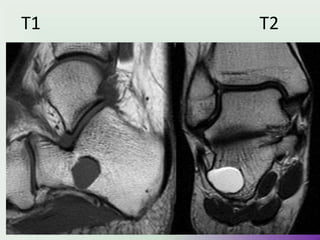

• MRI

• MRI is best at assessing

cartilage thickness (and thus

assessing for malignant

transformation), presence of

oedema in bone or adjacent

soft tissues and visualising

neurovascular structures in the

vicinity.

• The cartilage cap of

osteochondromas appears the

same as cartilage elsewhere,

with intermediate to low signal

on T1 and high signal on T2 and

STIR weighted images.

• A cartilage cap of over 1.5cm in

thickness is suspicious for

malignant degeneration.UMY

T1 T2 STIR

(FAT SUPPRESSION)